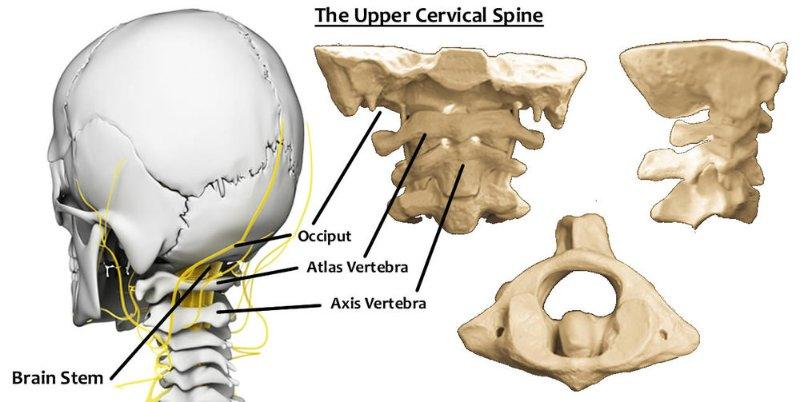

occiput or occipital region

- the hard region of the vertebrate cranium.

https://medical-dictionary.thefreedictionary.com/occipital+region

Original anzeigen (0,3 MB)Das Hinterhauptbein (auch Hinterhauptsbein; lat. Os occipitale [1] oder kurz Occiput) ist der am Halsübergang gelegene Teil des Hirnschädels. Es bildet den hinteren Abschluss der Schädelhöhle und mit dem Atlas das erste Kopfgelenk.

7. Hinterhauptbein (Os occipitale) (grün)Wikipedia: Hinterhauptbein